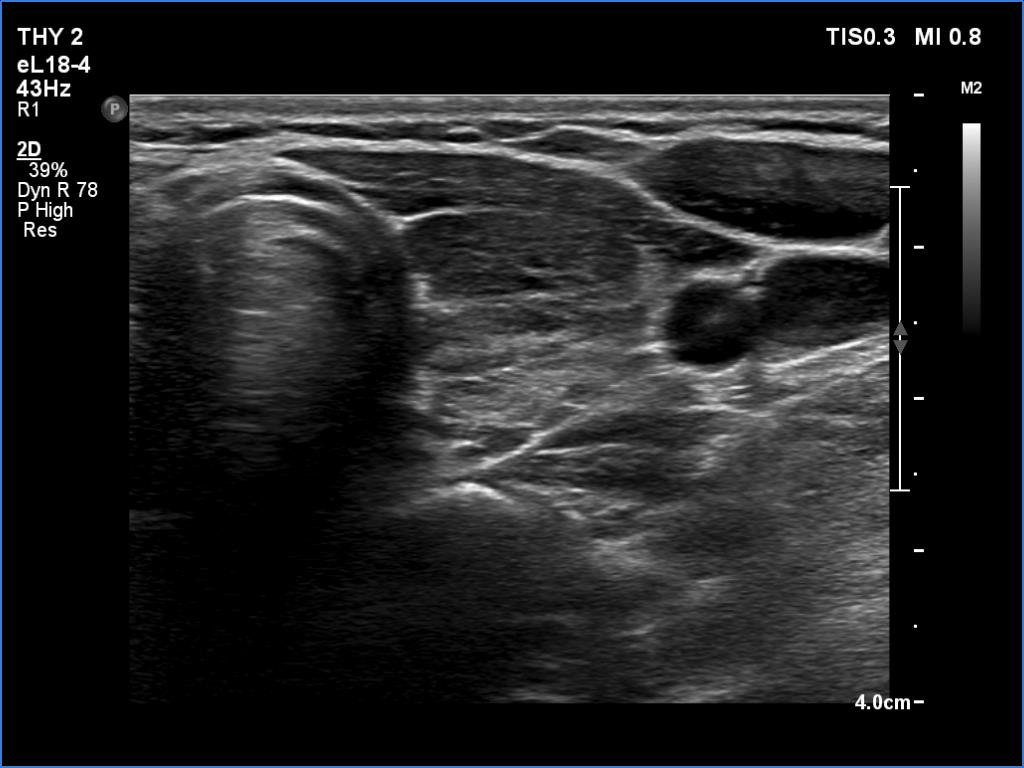

Lymphocytic thyroiditis - case 897

Examination one

Focal form of lymphocytic thyroiditis is presented. At the first examination, beside smaller hypoechoic areas, the left lobe had a larger discrete lesion. It was doubtful whether this should be regarded as pathological nodule or not. In the first case, the lesion is an EU-TIRADS 5 nodule due to the irregular margins while in the latter, this is an EU-TIRADS 1 lesion. Six months later, the lesion had virtually disappeared which means that this was not a true nodule.